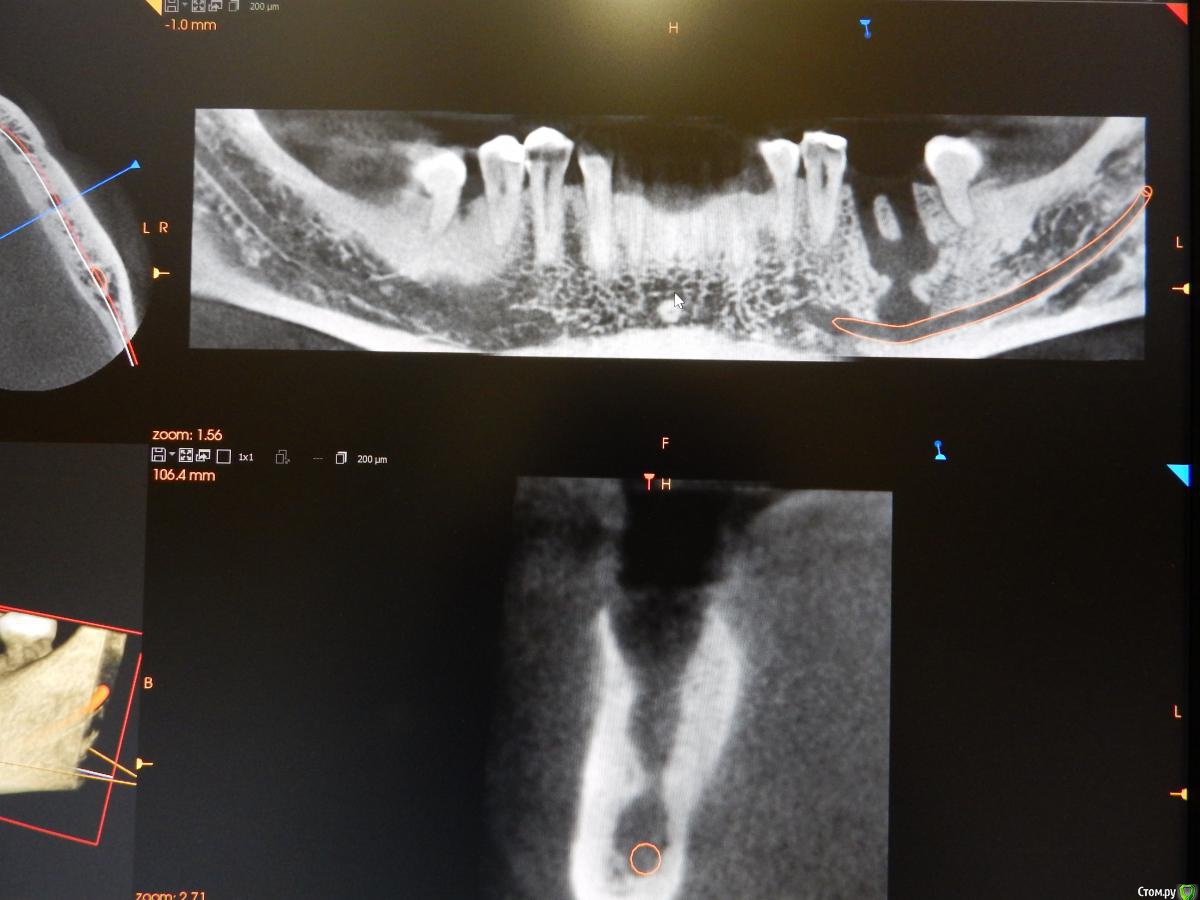

dantist_movani Опубликовано 8 октября, 2015 Поделиться Опубликовано 8 октября, 2015 Пациент обратился более 2 месяцев назад с жалобами на боли при накусывании, постоянные ноющие боли в зубе 3.6. Со слов больного зуб болел и ранее, но спасали НПВС, а тут 3 дня не может уснуть. Ранее зуб лечился (резорцин-формалиновый метод), перкуссия положительная, по переходной складке всё спокойно, лимфоузлы слева(поднижнечелюстные) чуть увеличены, при пальпации болезненны. Удалил, кюретаж, отделяемого никакого, под сгустком лунка зажила. Интраоральный снимок, делался в 2011 году, но зуб тогда болеть перестал. КТ на следующий день после удаления. Радикулярная киста? Какой план действий в данной ситуации? Ссылка на комментарий

dantist_movani Опубликовано 8 октября, 2015 Автор Поделиться Опубликовано 8 октября, 2015 ждем 3 месяца. потом им ждем 3 месяца. потом имплант.имплантат конечно хорошо, но меня пока волнует деструкция костной ткани! особенно то, что может быть вовлечен н/ч нерв Ссылка на комментарий

Чертков Александр Опубликовано 8 октября, 2015 Поделиться Опубликовано 8 октября, 2015 Ничего там не вовлечено! Рентген контроль через пару месяцев (желательно КТ) и болтокрутинг. 1 Ссылка на комментарий